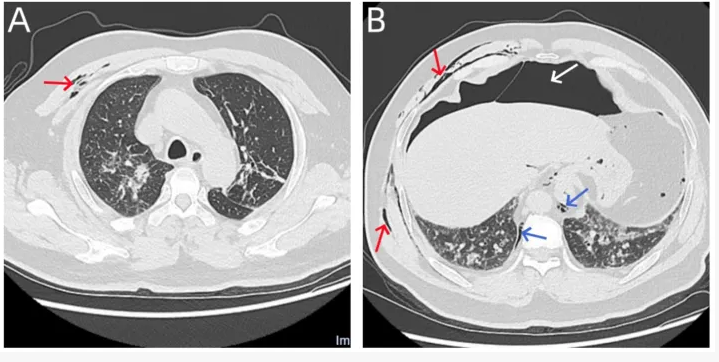

病例摘要: 一名51岁女性因咳嗽伴血痰7天入院。入院第8天,为检测下呼吸道可能存在的病原体,安排了支气管镜检查以进行支气管肺泡灌洗。检查过程中,通过一根12F鼻咽导管以5-10 L/min的流量输送氧气,导管尖端距鼻孔约5-6 cm。支气管镜检查开始4分钟后,患者突然呕吐约20 mL水,随后出现剧烈腹痛。体格检查显示明显腹胀、全腹硬韧及压痛,考虑为气腹,遂立即终止支气管镜检查。计算机断层扫描显示孤立性张力性气腹,遂置入引流管进行腹腔减压,患者症状随之缓解。多学科专家会诊讨论后建议进行剖腹探查,但最终被患者家属拒绝。患者无腹膜炎体征,最终于支气管镜检查后5天顺利出院,恢复良好。